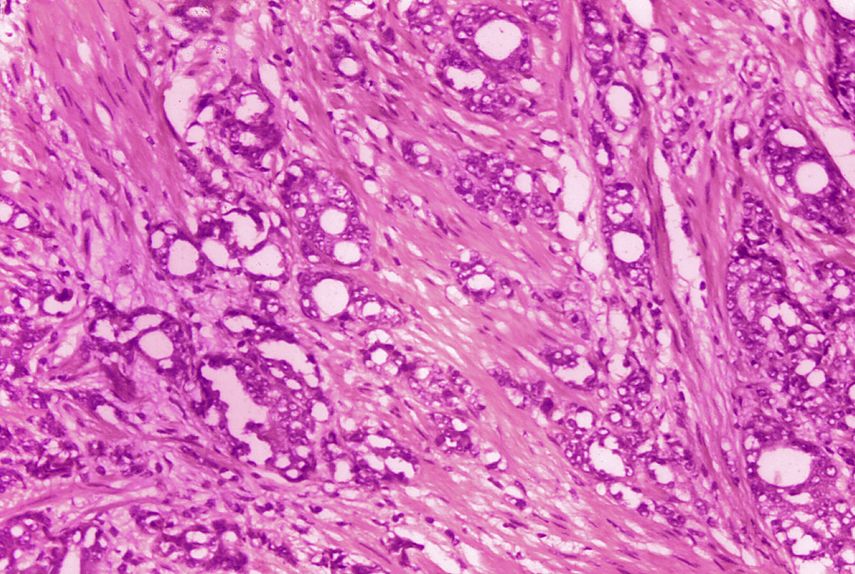

Cuando un paciente arroja un resultado sospechoso en el análisis, su médico podría recomendar hacerle una biopsia, en la que se toma una muestra de tejido de la glándula prostática. Después un patólogo la analiza al microscopio y determina si las células se ven normales o no.